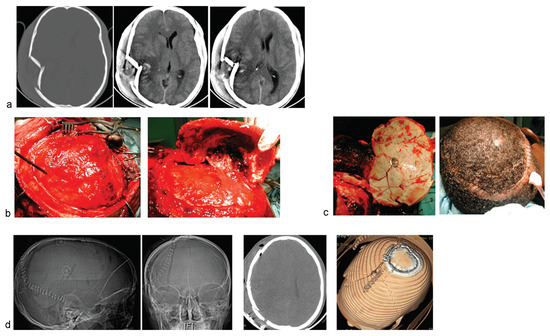

Figure 2.

Another case of comminuted right temporofacial skull fracture. (a) Cranial CT showing the depressed, comminuted skull fracture. There is only minimal contusion of underlying brain. (b) The fracture lines were exposed, and a craniotomy flap incorporating the fragments was raised. (c) The fracture fragments are first given thorough debridement, soaked in saline impregnated with antimicrobial, and finally refixed with the titanium clamp. (d) Postoperative cranial CT images showing excellent restoration of the craniofacial symmetry.